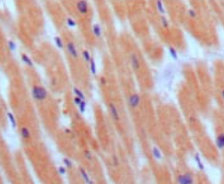

IHC    1/200 - 1/1000